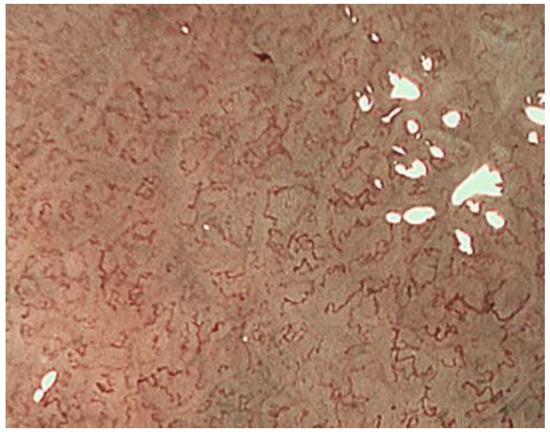

2.1. ME-NBI for Gastric Non-Cancerous Mucosa